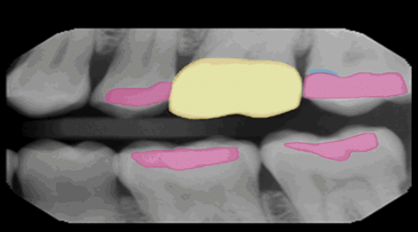

VELMENI for Dentists® 2D

VELMENI is as easy to use as it is powerful. Scan 2D radiographs to increase detection accuracy by 30%. FDA cleared for 2D Panoramic, Bitewing and Periapical X-Rays.